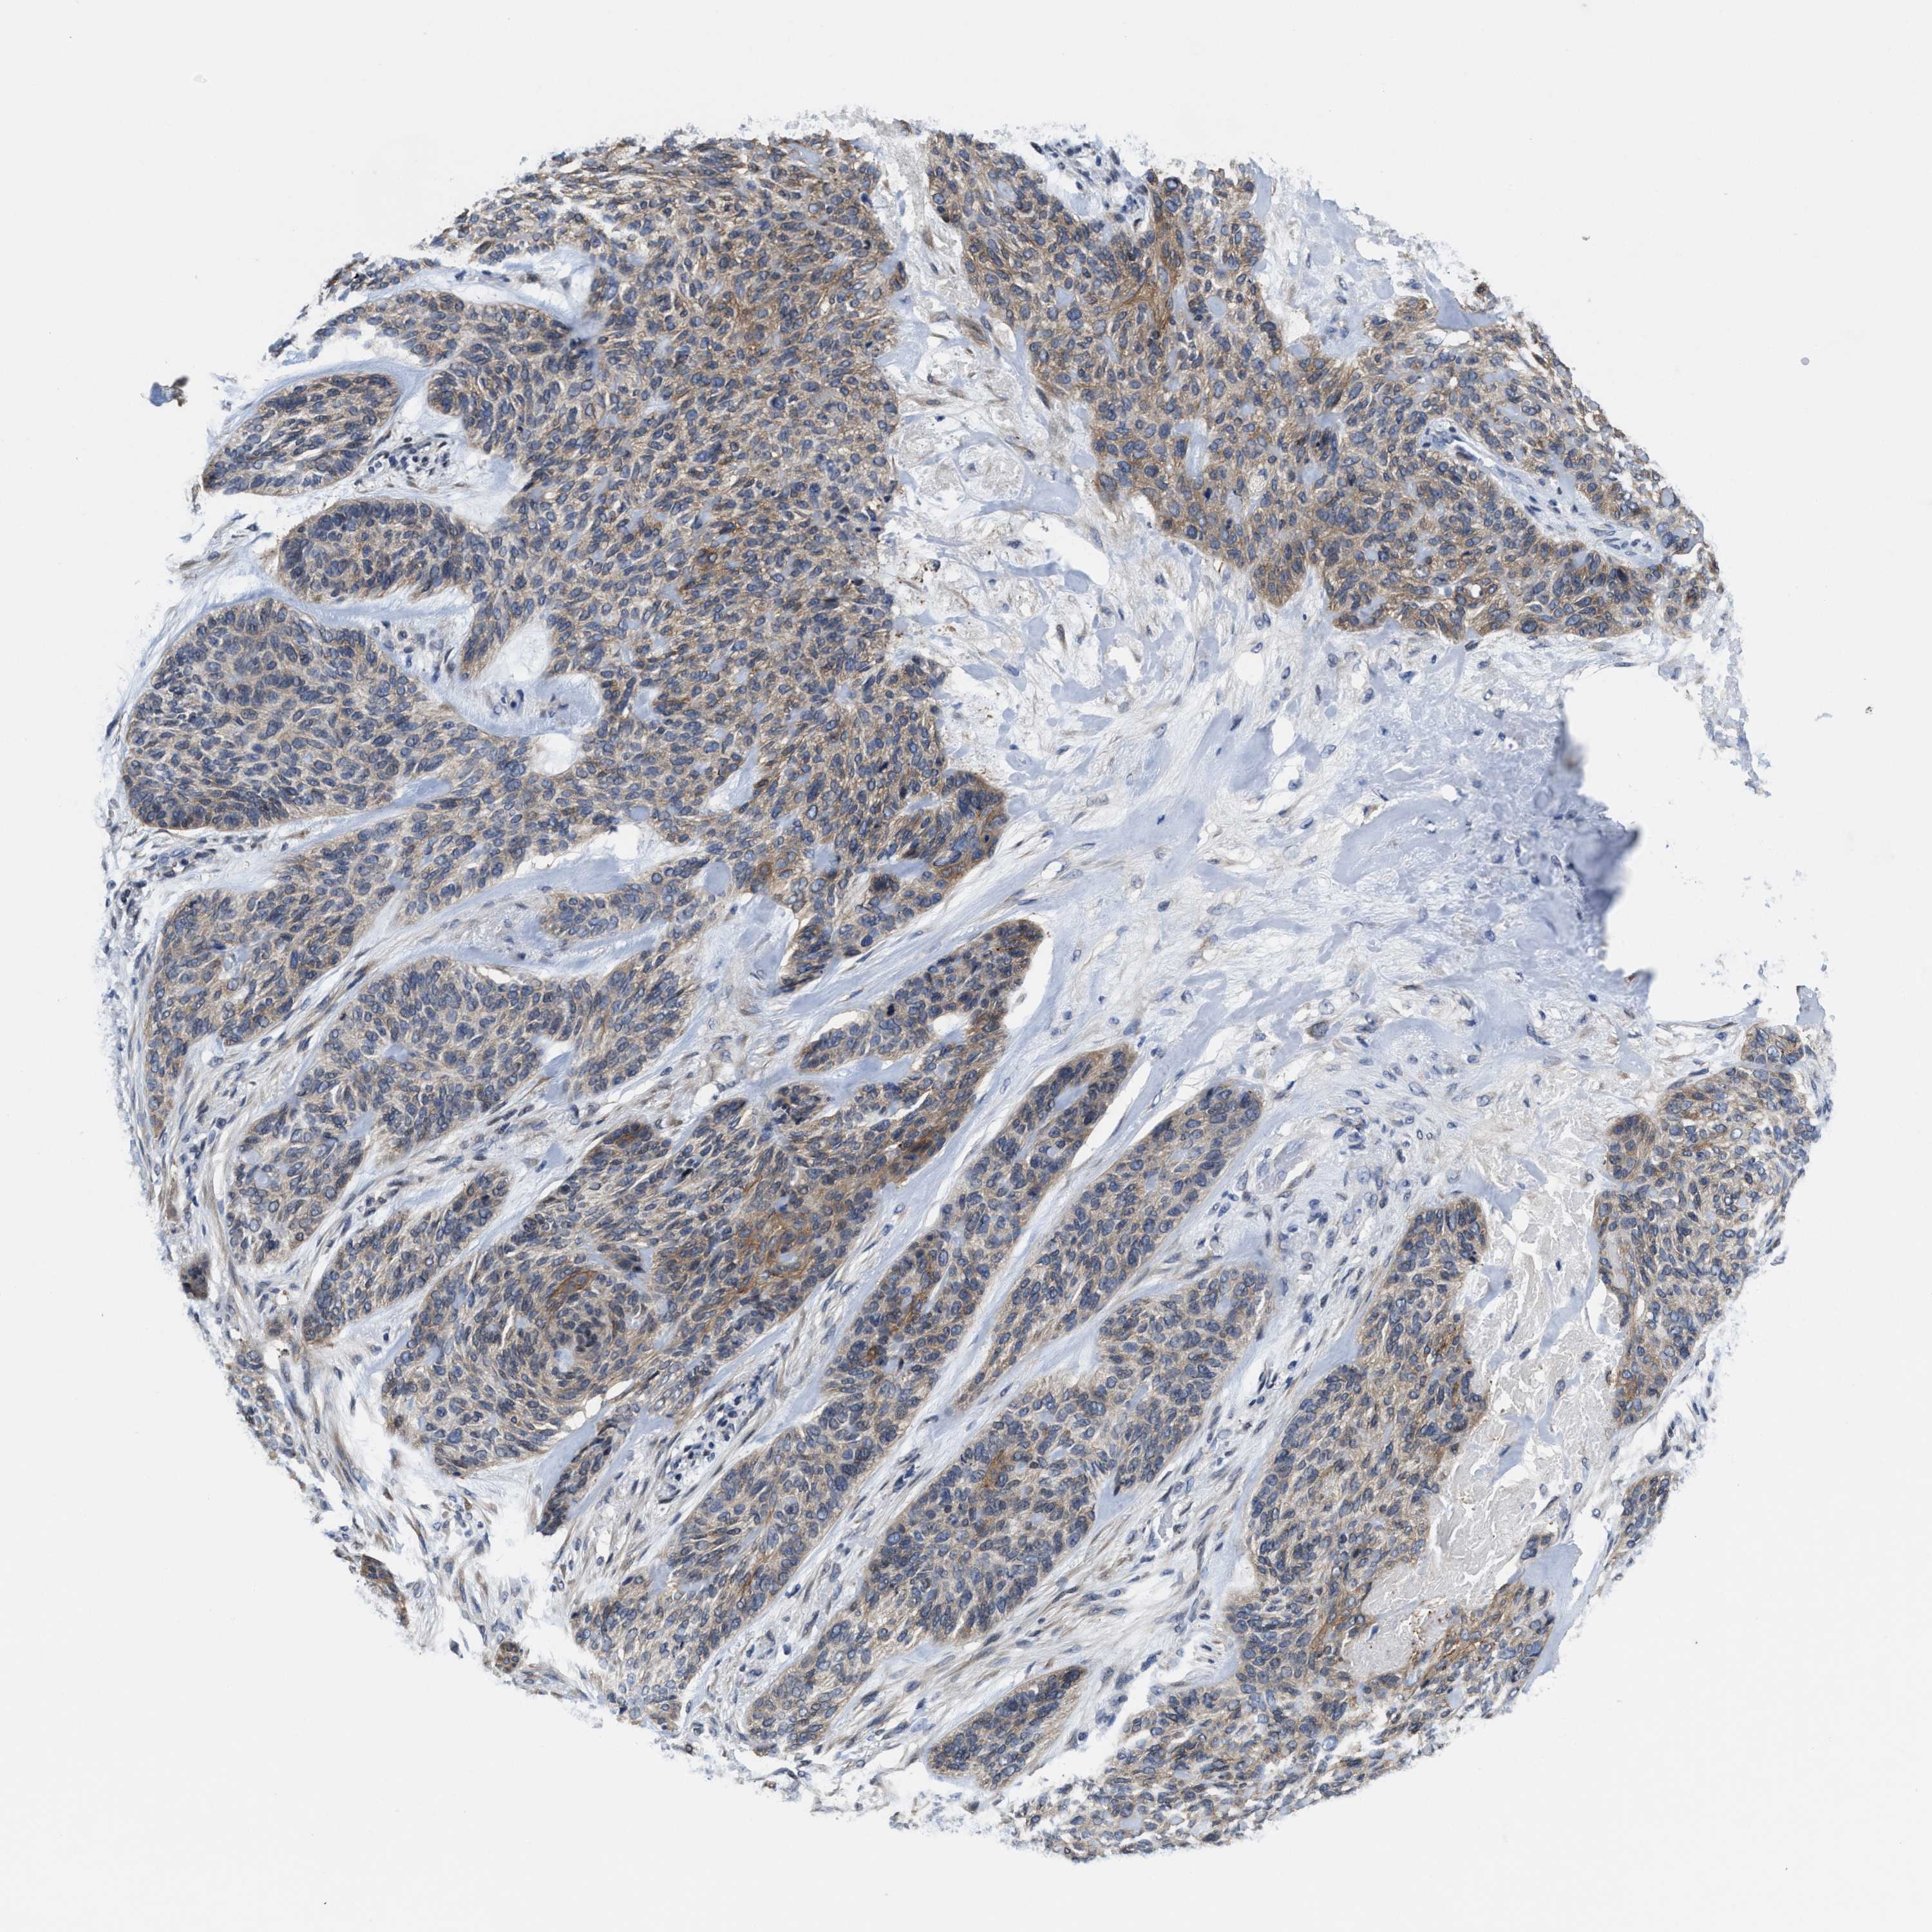

Basal cell and squamous cell cancer

SKIN CANCER - Protein expressioni

A mouse-over function shows sample information and annotation data. Click on an image to view it in a full screen mode. Samples can be filtered based on level of antibody staining by selecting one or several of the following categories: high, medium, low and not detected. The assay and annotation is described here.

Antibody stainingi

Antibody staining in the annotated cell types in the current human tissue is reported as not detected, low, medium, or high, based on conventional immunohistochemistry profiling in selected tissues. This score is based on the combination of the staining intensity and fraction of stained cells.

Each image is clickable and will lead to virtual microscopy that enables deeper exploration of all samples and also displays staining intensity scores, fraction scores and subcellular localization as well as patient and tissue information for each sample.

Antibody HPA020192

Antibody HPA024127

Staining

High

Medium

Low

Not detected

Intensity

Strong

Moderate

Weak

Negative

Quantity

>75%

75%-25%

<25%

None

Location

Nuclear

Cytoplasmic/membranous

Cytoplasmic/membranous,nuclear

Squamous cell carcinoma, NOS